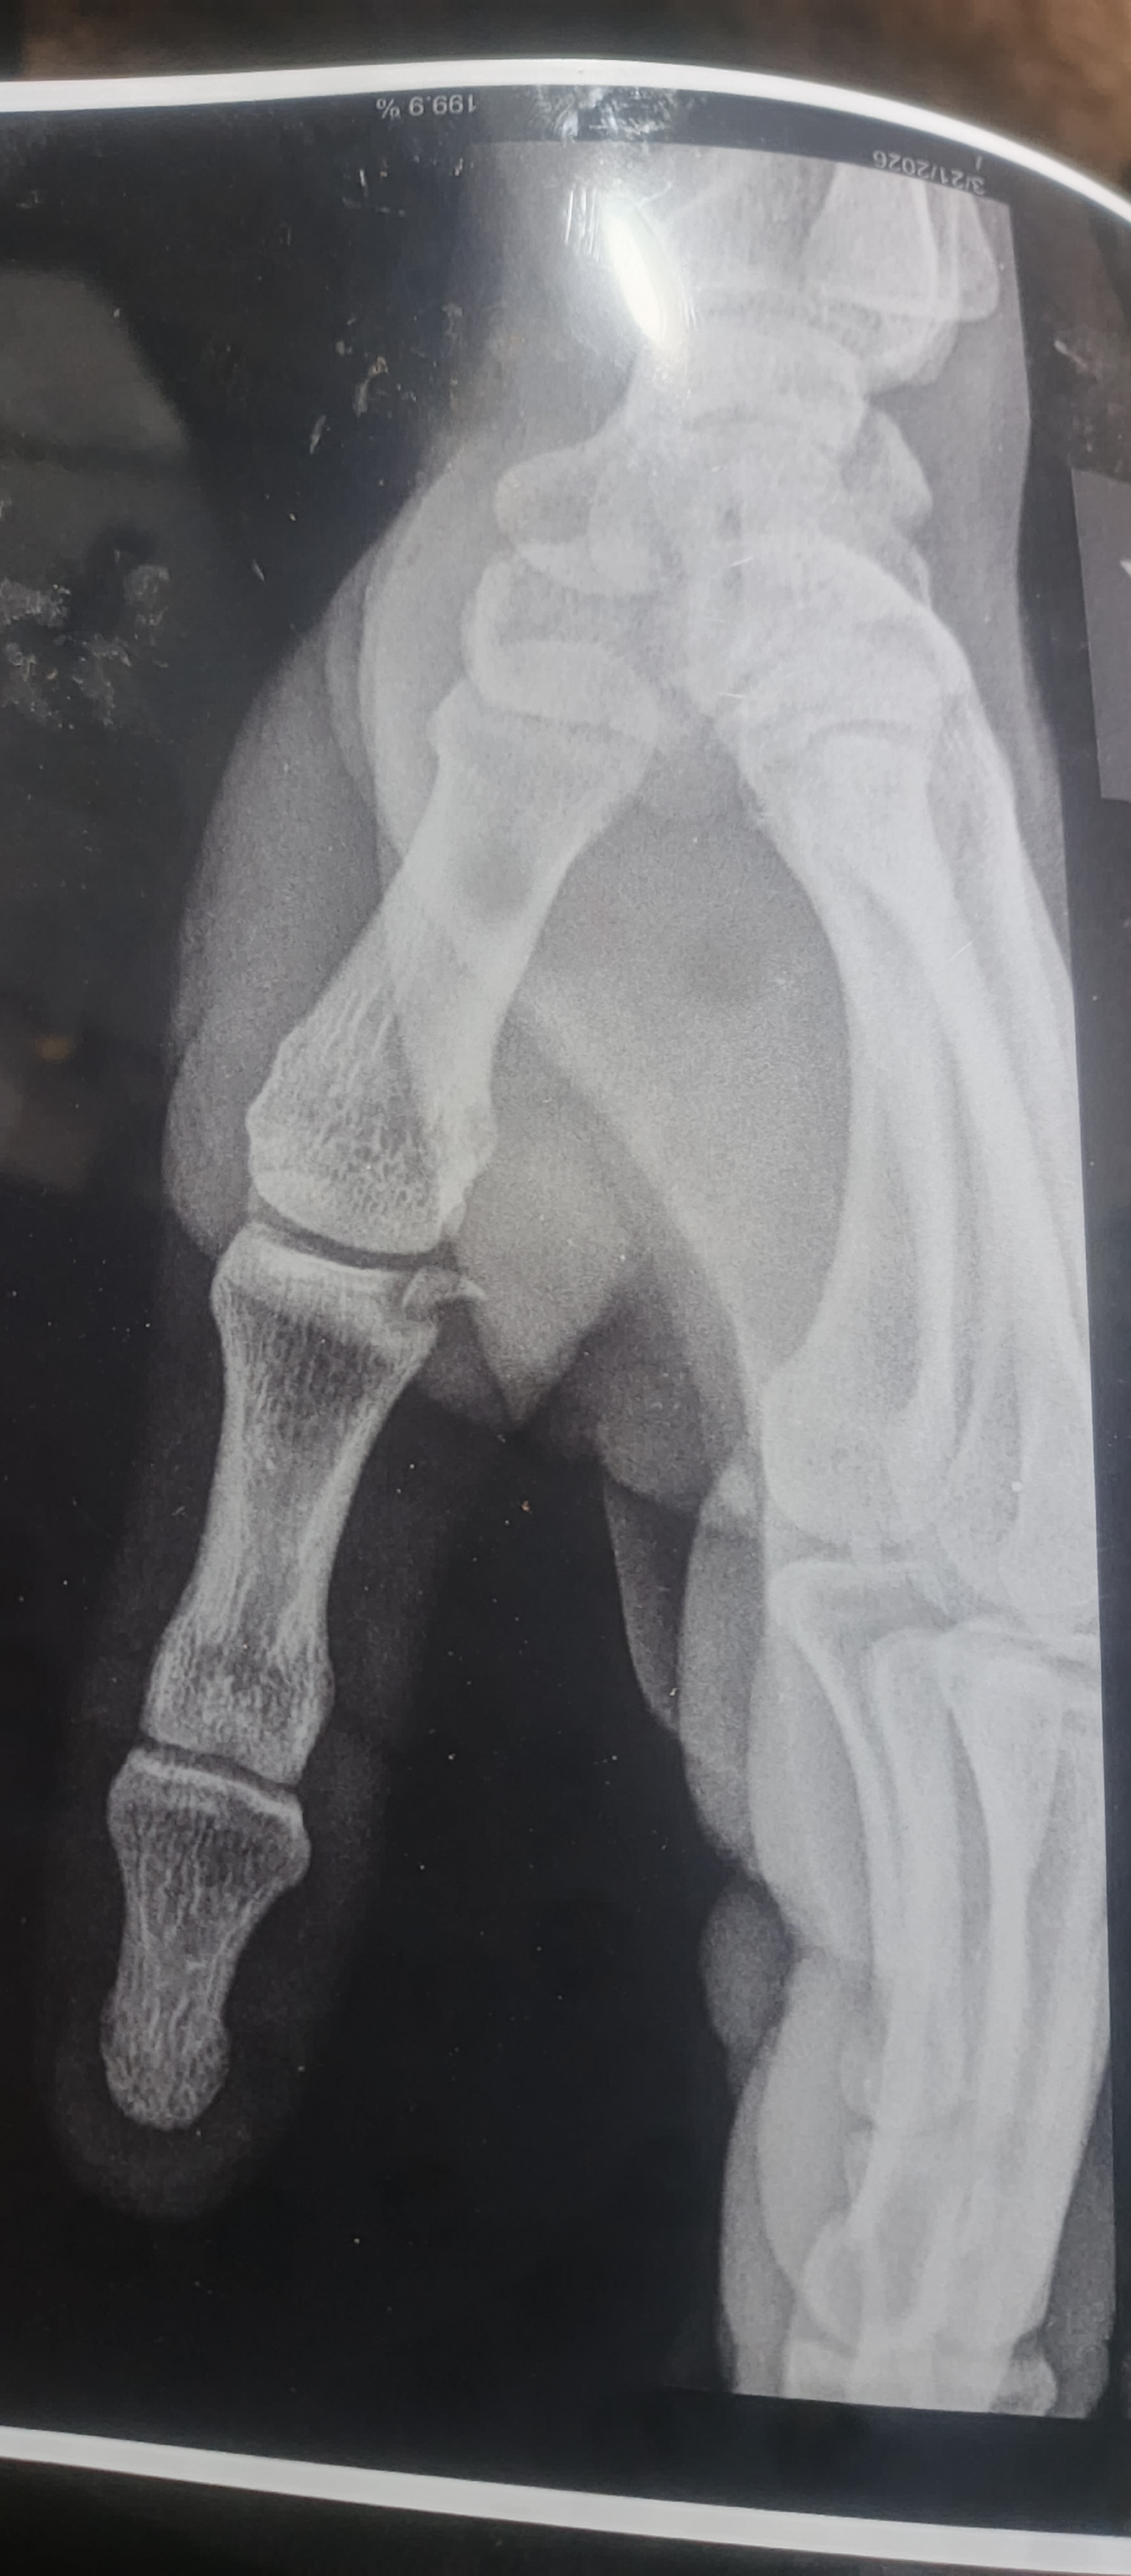

دكتور ممكن تشوف الصوره وتقولي ايش تحتاج وكم التكلفه

كسرت يدي قبل شهران والان اصبحت تؤلمني قمت بتصوريها اتمنى انت تريني ماذا تحتاج؟